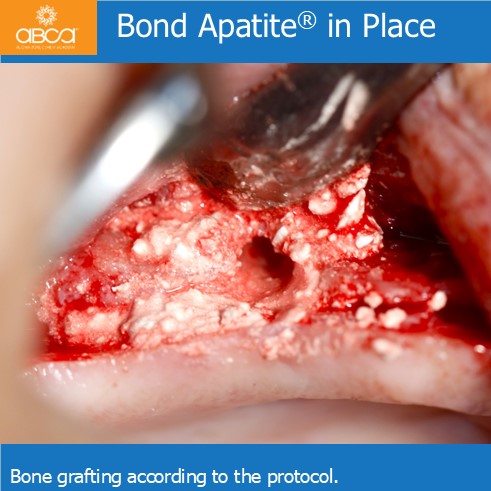

Sinus lift with Augma Lift™ Kit B with 4-5 mm sub sinus bone height.

Sinus lift with Augma Lift™ Kit B with 4-5 mm sub sinus bone height. A young woman came to replace the missing first maxillary molar with moderate atrophy.

Sinus lift with Augma Lift™ Kit B in a case with 5 mm sub sinus bone height.

Sinus lift with Augma Lift™ Kit B in a case with 5 mm sub sinus bone height. The patient came for implant treatment in the region of teeth #16 (3)…

Sinus lift with Augma Lift™ Kit B in a case with missing teeth #14 (5), #15 (4), #16 (3), #17 (2) and a sub sinus bone height of 6 mm.

Sinus lift with Augma Lift™ Kit B in a case with 6 mm sub sinus bone height.